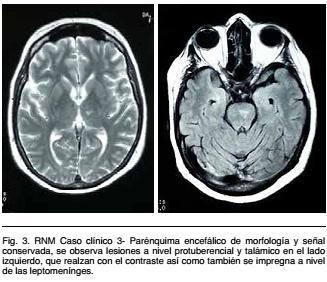

Angio RNM encefálica: parénquima encefálico de morfología y señal conservado, se observan lesiones a nivel proturebancial y talámicos en el lado izquierdo, que realzan con el contraste así como también se impregnan a nivel de leptomeninges compatibles con vasculitis. Angiografia no evidencia lesiones (Figura 3).